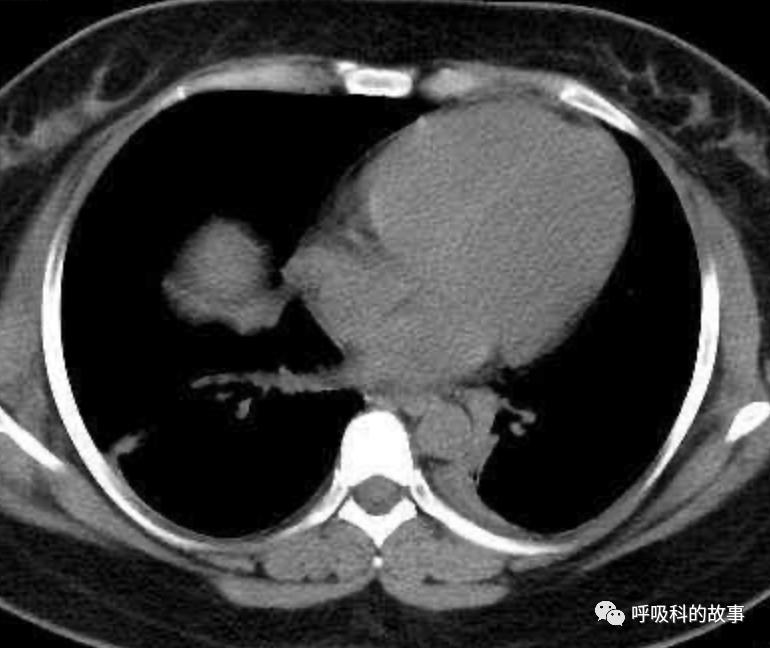

可是在6月26日(往院第18天)仍持续发热的情况下复查肺部CT,肺部病灶已明显吸收了。那么患者发热的原因到底是什么呢?为什么患者高热的情况下血白细胞不升反降,C反应蛋白也没有明显增高?这个时候消化科医生也迷茫了,这可怎么办?于是请感染科和呼吸科医生一起会诊,共商计策。